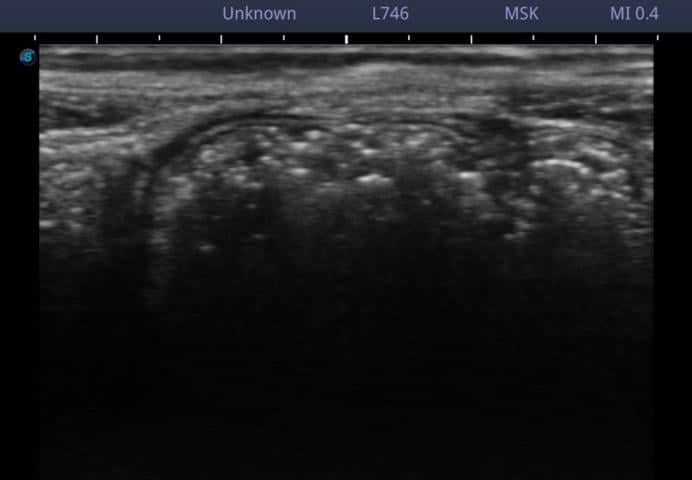

腹直筋離開のエコー写真

腹直筋の間にある白線が、延長しており、薄くなっているのが観察されます。